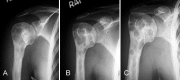

We reviewed 87 patients with giant-cell tumor treated between 1992 and 2001. The mean follow-up was 62 (28-138) months. Fifty-six lesions were treated with intralesional curettage with adjunctive phenol treatment and reconstructed with autograft and allograft. Thirty-one lesions were treated with wide resection and reconstructed with prosthesis, osteochondral allograft, or alloprosthetic composite. Overall recurrence was 12%. Recurrence rate after curettage was 18% and 3% after wide excision. Complication rate after wide excision was higher than that after curettage. Functional outcome was evaluated using the Enneking scoring system. Average rating was 86% for the lower extremity and 83% for the upper extremity. The overall satisfactory rate was 88%.